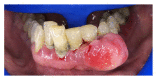

Results: The studies taken into consideration evaluated different factors, such as OHRQoL, QoL, and oral alterations, involving soft tissue, dental structures, and postrehabilitative complications, as well as immunological alterations.